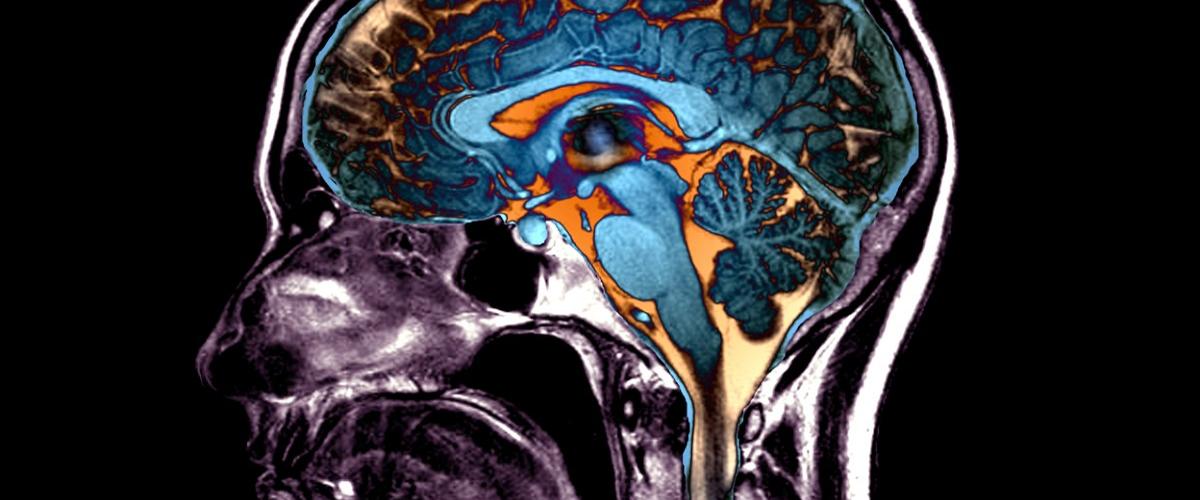

Старение изменяет анатомию мозга, однако человеческий глаз не способен воспринимать и отслеживать закономерности систематических изменений ткани. Ученые из США решили применить для этих целей алгоритм искусственного интеллекта и с его помощью выявили пять различных закономерностей атрофии головного мозга, связанных со старением и распространенными заболеваниями, пишет Nature.

На первом этапе алгоритм обучали на МРТ снимках 10 тыс. здоровых людей и пациентов с нарушениями когнитивных функций. Это позволило создать карты анатомических структур, которые изменяются в мозге при наличии или отсутствии заболевания. На втором этапе потенциал ИИ оценили на снимках 50 тыс. добровольцев. Вместе данные позволили создать пять четких моделей старения мозга человека.